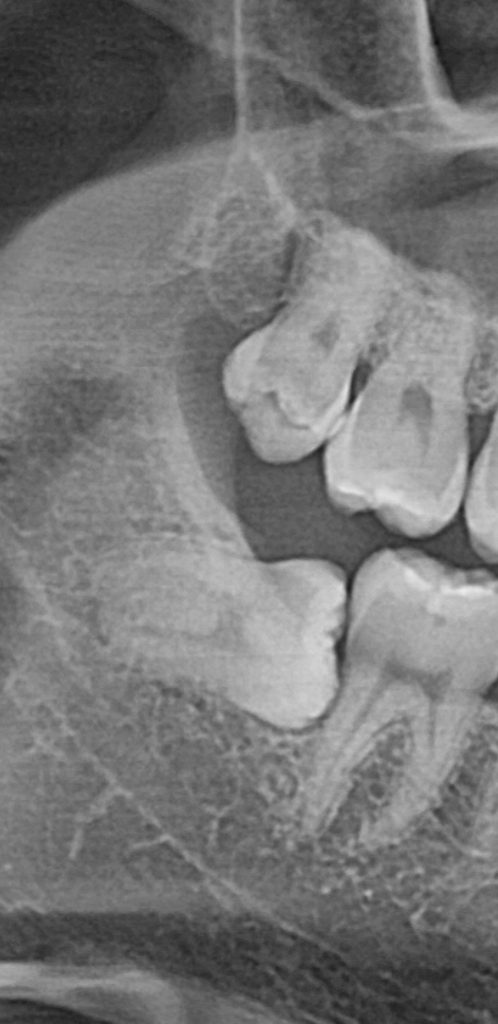

다만 아래 사랑니도 뽑아야되나 싶어서 고민입니다

사랑니 머리가 아주 조금 튀어나와있고

왼쪽도 오른쪽도 수평매복사랑니라서 치유 기간도 오래 걸릴텐데

현재 사진에는 이상이 없겠지만 지금 상태에서 뽑는 것이 좋습니다. 지금 상태의 사랑니는 문제가 생기면 앞쪽 어금니도 손상시킬 수 있습니다. 따라서 통증이나 불편감이 없을 때 미리 발치하는 것을 추천드립니다. 가능하면 즛앙이 없을 때 뽑는 것이 좋습니다.

아래 매복 사랑니는 발치 하는게 좋습니다. 인접치아의 치근흡수, 인접치의 이동, 악궁의 공간소실, 치아낭종 형성, 매복 주변 부위의 감염 및 통증, 림프절부종, 음식물을 씹을 때 매복치 주위에서 불쾌한 입맛, 입을 열때 불편감, 턱 뼈의 통증 등을 유발 할수 있기 때문입니다.

기울어져 나고 있는 사랑니의 경우에는 앞에 이물질이 저류하게 되어 앞의 치아에 충치를 발생시킬가능성이 높아요.

음식물이나 이물질이 잘 저류할수 있어서 앞에있는 치아와 치주조직에 안좋은 영향을 미치게 될가능성이 있다면 예방차원에서 발치를 하는것이 좋습니다.